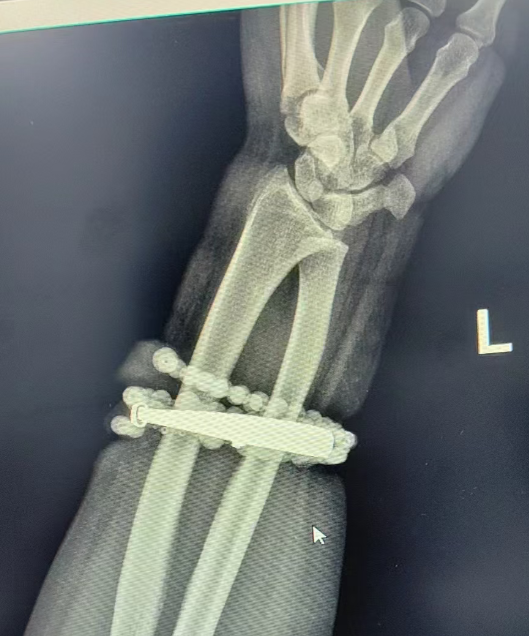

33岁的龚女士(化名)手腕上的银手镯和串珠戴了近十年,几乎从未摘下来过。随着体重增加,龚女士手腕逐渐被勒得紧绷,但未引起重视。

直到两周前,龚女士手腕疼痛加剧,红肿明显并伴有脓液渗出,她才惊觉手镯和串珠已部分“长”入肉中,无法自行取下,随即到医院就诊。

“这是典型的首饰长期压迫、摩擦,加上细菌感染,引发的慢性炎症和肉芽组织增生。”医生介绍,若不及时取出并彻底清创,感染可能向深部蔓延,甚至诱发败血症或影响前臂功能。

经过一个多小时的手术,医生们将手镯和串珠从厚厚的增生组织中完整剥离出来。目前,龚女士恢复良好,已顺利出院。